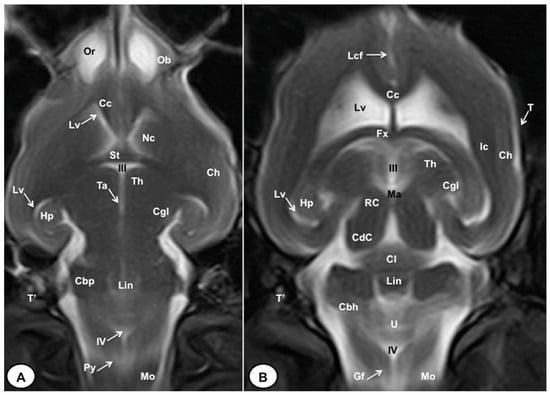

3.1. Anatomical Cross-Sections

3.2. Magnetic Resonance Imaging (MRI)